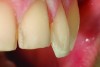

Fig 4. After apical repositioning of the gingival margin over tooth No. 4 with a diode laser, the overcontouring of the porcelain to accommodate the preoperative gingival position is evident. The excessive emergence profile on the disto-proximal aspect of the veneer restoration has caused a chronic marginal periodontitis in the area so that bleeding is always present regardless of the level of home care.

Figure 4